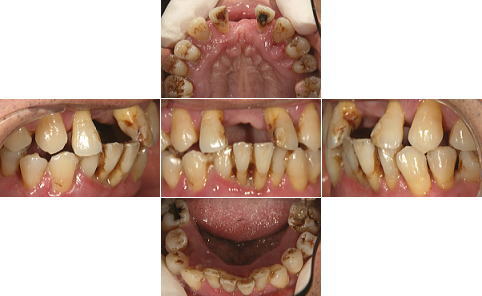

| 治療前 | 治療後 |

| 下顎の前歯部以外の全ての歯にグラツキがあったため、上顎はAll-on-4、下顎の奥歯は通常のインプラントブリッジとしました。 | |